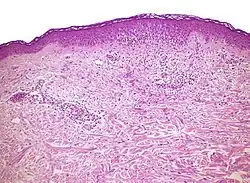

Vacuolar interface dermatitis (VAC, also known as liquefaction degeneration, vacuolar alteration or hydropic degeneration) is a dermatitis with vacuolization at the dermoepidermal junction, with lymphocytic inflammation at the epidermis and dermis.[1]

| Generally/Not otherwise specified | Typical findings, called "":[2]

An interface dermatitis with vacuolar alteration, not otherwise specified, may be caused by viral exanthems, phototoxic dermatitis, acute radiation dermatitis, erythema dyschromicum perstans, lupus erythematosus and dermatomyositis.[2]